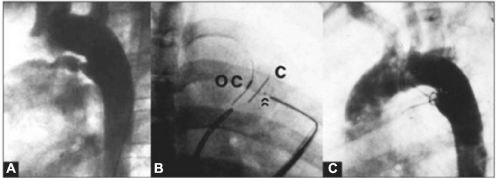

Na figura abaixo, observa-se uma oclusão de canal arterial. A: Canal arterial calibroso do tipo D; B: A imagem em oblíqua anterior direita mostra o dispositivo abotoado antes da liberação. As setas indicam o botão do oclusor abotoado no contra-oclusor; C: Aortografia de controle, demonstrando ausência de fuga residual.